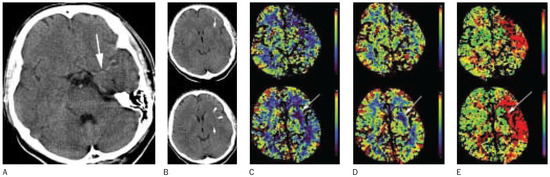

Intraarterial thrombolysis and the role of intensive care in acute ischaemic stroke

by M. Arnold, L. Remonda, K. Nedeltchev, U. Fischer, M. Sturzenegger, G. Schroth and Heinrich P. Mattle

Thrombolytics have the potential to reduce disability of acute ischaemic stroke patients without increasing mortality, if patients are carefully selected. Per 1000 patients treated 110–150 less will be disabled. Intravenous thrombolysis with recombinant tissue plasminogen activator (rt-PA) given within 3 hours after stroke [...] Read more.

Thrombolytics have the potential to reduce disability of acute ischaemic stroke patients without increasing mortality, if patients are carefully selected. Per 1000 patients treated 110–150 less will be disabled. Intravenous thrombolysis with recombinant tissue plasminogen activator (rt-PA) given within 3 hours after stroke onset has been shown to reduce the rate of long-term-disability significantly. The clinical benefit of intraarterial thrombolysis in acute stroke patients with M1 or M2 occlusion of the middle cerebral artery, when performed up to six hours of symptom onset, has recently been proved in a randomised trial. In addition, several case series indicate that intraarterial thrombolysis and intravenous thrombolysis can be administered safely in clinical practice and improve clinical outcome when the occluded vessel is recanalised. In acute stroke due to basilar artery occlusion intraarterial thrombolysis is a therapeutic option at longer time intervals in specialist stroke centres. Several series of patients with basilar artery occlusion suggest that intraarterial thrombolysis has the potential to enhance the chances of basilar artery recanalisation and improve clinical outcome. In some of these studies, using various thrombolytic agents and intervals to treatment, an association between vessel recanalisation and clinical outcome was described. The percentage of patients with a favourable functional clinical outcome is more than 50% when early recanalisation of the basilar artery can be achieved and very low when the artery remains occluded. To date, no randomised controlled trial has compared intraarterial thrombolysis and intravenous thrombolysis. Intraarterial thrombolysis has several advantages: arteriography assesses the complete vessel status and collateral circulation. The thrombolytic medication can be applied directly into the thrombus.Vessel recanalisation as well as reocclusion are visualised directly, and in the case of rapid recanalisation, the infusion of the thrombolytic drug can be stopped before the maximum dose is applied. If pharmacological thrombolysis cannot be achieved, mechanical recanalisation procedures like thrombus perforation, thrombaspiration or percutaneous transluminal angioplasty are alternative or adjunctive strategies. In addition, mechanical recanalisation can sometimes be timesaving and achieved within a few minutes and faster than pharmacological reopening of the vessel. Limitations of intraarterial thrombolysis include the potential risk of arteriography, the time delay due to diagnostic arteriography and that it can only be applied at institutions with an experienced interventional neuroradiology team. Bleeding represents a hazard as with intravenous thrombolysis. Another major advantage of intraarterial thrombolysis is the extended time window up 6 hours compared to the 3 hours of intravenous thrombolysis.Therefore, intraarterial thrombolysis increases the number of patients who are eligible for thrombolysis. Nevertheless, campaigns and protocols for early referral to stroke centres and a standardised treatment algorithm are urgently needed. Educational programs for both the physicians and the public have the potential to increase the percentage of patients admitted to stroke centres within the time window for thrombolysis. Full article